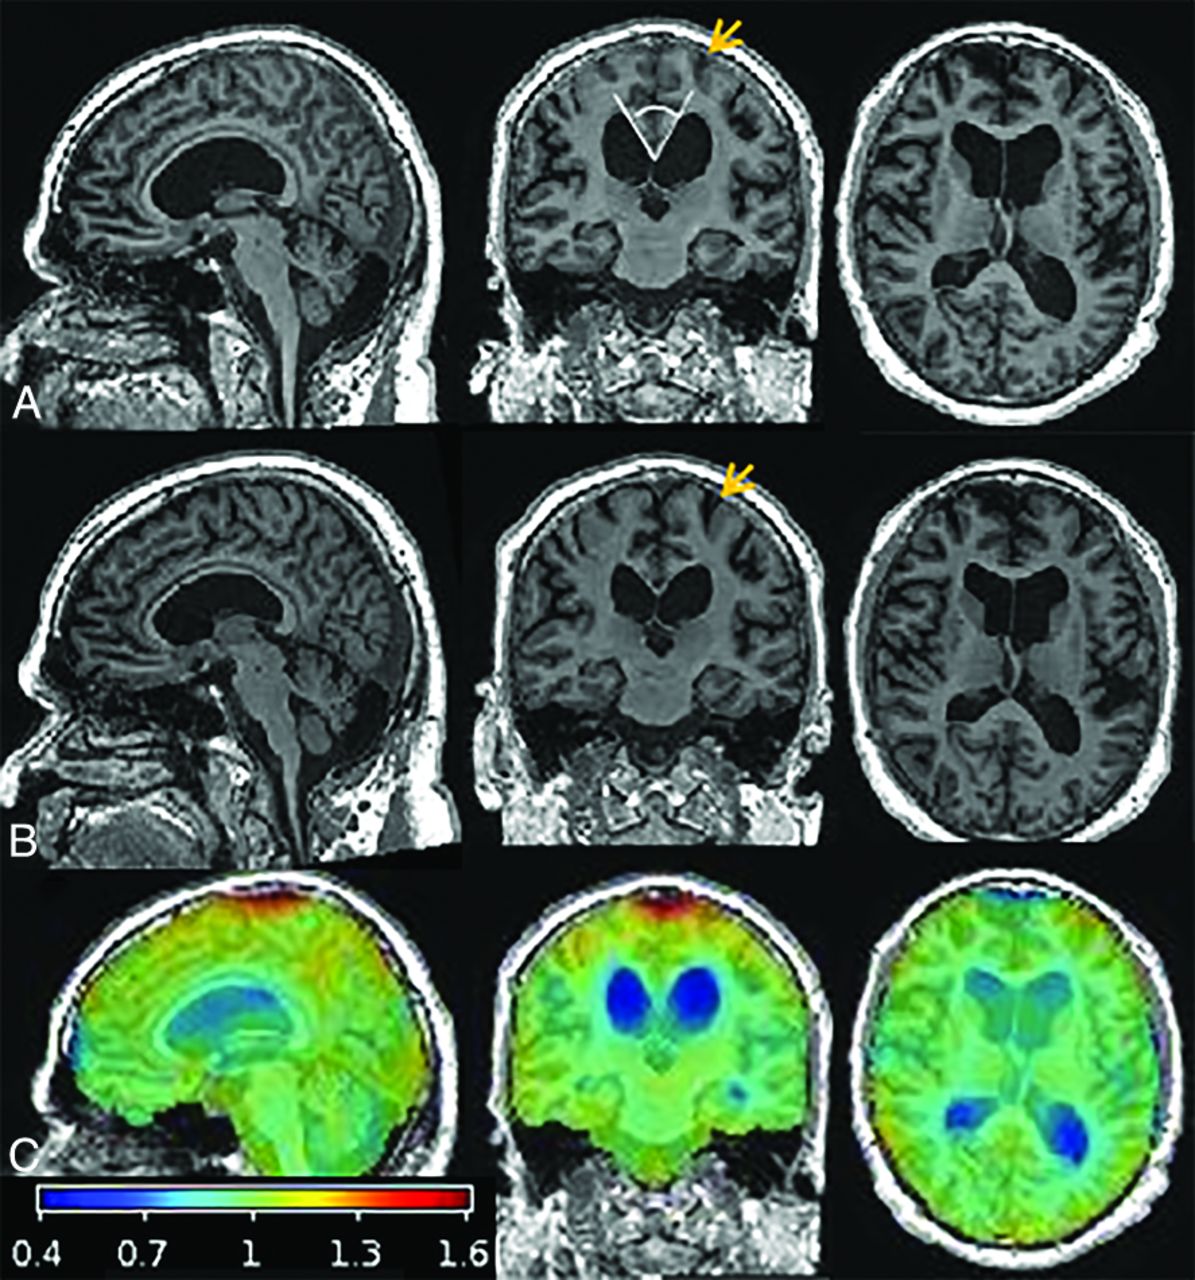

T1-weighted MR imaging and overlaid Jacobian maps of estimated changes between pre- and postshunt imaging for a representative patient, a 66-year-old man with iNPH. Sagittal, coronal, and axial slices of pre- (A) and postshunt (B) T1WI after registration to the patient’s common mean and differential bias correction. C, Map of voxelwise Jacobian determinants overlaid on the preshunt T1WI to demonstrate changes that occurred after shunt placement by warping the late-to-early image: The ventricles contracted (blue) and CSF spaces at the vertex and surrounding parenchyma expanded (red and orange). Although changes in parenchymal volume are not visibly apparent on the T1WI, the coronal images demonstrate decreased crowding of the sulci at the vertex after shunt placement (orange arrows), corresponding to regions that showed an increase in cortical volume after shunt placement. The callosal angle measurement is demonstrated in the coronal image in row A (white lines).

Global Volume Changes

Pre- and postshunt T1WI with overlaid Jacobian determinant maps are shown for a representative patient in Fig 1. The estimated mean voxelwise percentage change in volume (log-Jacobian) from pre- to postshunt MR imaging among all patients is shown in Fig 2; the scale is compressed relative to the Jacobian maps in Fig 1, to better show regional parenchymal changes. The voxelwise maps demonstrated the global changes that occurred after shunt placement throughout the brain parenchyma, ventricles, and CSF spaces, including regions not specifically evaluated in regional analyses. The CSF spaces and parenchyma near the midline vertex expanded after shunt placement. The ventricles and Sylvian fissures contracted after shunt placement, and there were regions of parenchymal contraction at the anterior-inferior frontal and temporal lobes.